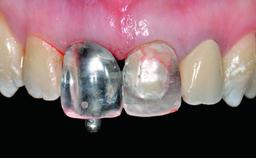

Replacement of a Compromised Upper Right Central Incisor: Hard- and Soft-tissue Augmentation, Late Placement of an RC Bone Level Implant

A 36-year-old male patient with a compromised maxillary central incisor was referred by his general dentist for consultation. The patient’s chief complaints were the gradual debonding of a temporary crown on the right central incisor and unsatisfactory esthetics due to an increasing diastema between the right central and lateral incisors. The patient reported a traumatic event some years previously, when a crown had been placed after root-canal treatment. The referring dentist wanted to provide a new crown restoration, but was concerned about the condition of the residual root. Anamnesis was negative for any other dental or periodontal pathology in the remaining dentition. The patient reported taking no medications: He was a smoker (10 to 15 cigs/day) and had realistic esthetic expectations.

Prosthesis Type FDP

Retention Screw-retained Screw-retained